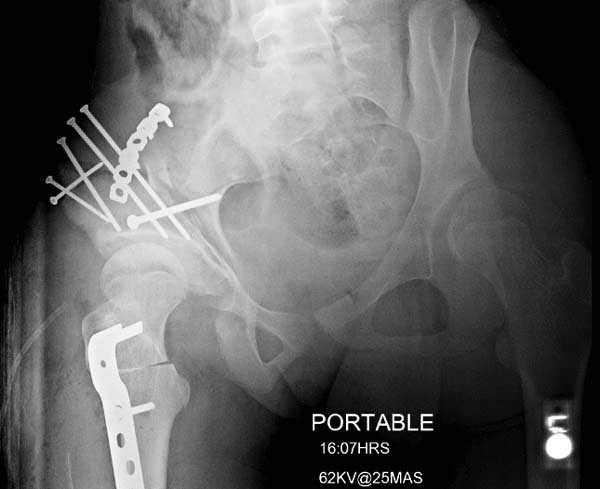

Жалобы на двухсторонние постоянные боли при нагрузке и неустойчивость. Внутренная ротация конечности в суставе более 40 градусов и на рентгенограмме двухсторонний подвывих головки с нарушением линии Шентона, а на боковом снимке с минусовым покрытием головки. МРТ - удлиненная связка и импинджмент (бугор) в шейке.

Первым этапом сделана подготовка к ротационной межвертельной остеотомии, затем капсулотомия с удалением импинджмента и периацетабулярная остеотомия с 40 градусной экстензией и операция закончена 35 градусной наружной ротацией бедра. Запланированный варус не сделан из-за относительно нормального покрытия головки.

Одним из преимуществ ПАО является сохранение задней колонны, и всю фиксацию в основном делают спереди из крыла подвздошной кости. При реконструкционных операциях по поводу дисплазии редко коррекция превышает 25 градусов, и достаточной бывает фиксация тремя шурупами вертикально сверху вниз, и один между колоннами спереди кзади. Но у нашего пациента серьезные изменения, и для достижения результата надо было около 40 градусов коррекции, из-за чего в линии остеотомии создалась ступенька. Для предупреждения скольжения дополнительно установлена buttress пластина, которая зафиксирована только в одном сегменте, а другие два шурупа удерживают ASIS. Без остеотомии Anterior Superior Iliac Spine невозможен доступ внутри таза.